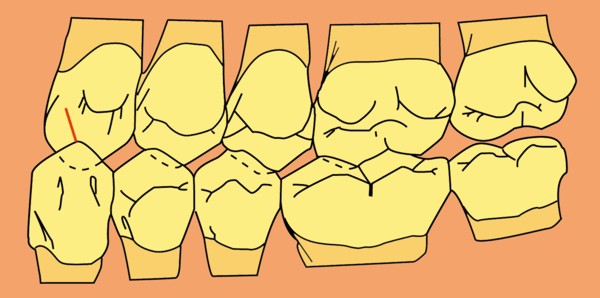

RESUMEN Más allá en el tiempo, respecto de las razones más frecuentes de fracasos como temperatura de fresado, infecciones, falta de fijación inicial, falta de higiene, etc., la OCLUSIÓN recibe sobre sí, la responsabilidad de la permanencia de la osteointegración, como así de la ortofunción del sistema todo. Sometimes ago,conserning the most frecuent reason of failures such as the strawberry action temperature, infections and lack of hygiene…etc.,the OCLUSION has itself the responsability af having the osteointegration well as the allsistem ortofunction . DESARROLLO La valoración de los fracasos en IMPLANTOLOGÍA es difícil de contabilizar sobre todo después del año, ya que el confort logrado por lo general, hace que el paciente realice correctamente sus primeros controles, y después; apoyado en su bienestar; intente subconscientemente olvidar ese período de su vida, que si bien le devolvió su capacidad masticatoria, fonética, social, etc., le ocasionara gastos, molestias, sufrimientos. … la APLICACIÓN de dichas fuerzas, requiere de una exactitud mucho mayor. Los esquemas propuestos a través de los años, no son muchos ni muy variados… I-Evitar las fuerzas tangenciales. II-Repartir las fuerzas lo máximo posible. Sin embargo, muchas veces se confunden los conceptos anteriores con criterios inexactos. Por ej: a-Reducción de las caras vestibulares y palatinas, aceptando que la menor superficie de intercontactos reduce la carga. b-Utilización de la Función de Grupo Posterior, en la creencia de que repartiendo el esfuerzo en las piezas posteriores, ganamos resistencia; a la potencia ejercida por los músculos. c-No permitiendo el contacto excéntrico de un canino implantado, para aliviarlo de las cargas laterales, sobre cargando de esta manera la tabla premolar-molar en el Lado de Trabajo. Algunos conceptos aislados, que forman parte de toda una filosofía de la Oclusión (OCLUSIÓN ORGÁNICA), sean tal vez de ayuda para echar luz sobre los preceptos anteriores. 1º-PROPORCIONES FUNCIONALES DE UN PAR OCLUSAL En la figura siguiente, observamos la relación final masticatoria de un PAR OCLUSAL: En el se ven los contactos puntiformes, producto del choque de superficies redondeadas contra superficies redondeadas («Solo pueden encontrarse en un punto» Ref: Principios Mecánicos Esferoidales.W.Mc.Horris.) Si Miramos con atención este tipo de contactos interoclusales, veremos que la superficie actuante es mucho menor que la superficie total de la cara oclusal: 45% (Fig.1) Por lo tanto, si no es por razones del Pilar de Emergencia para no crear un espacio biológico inadecuado… ¿POR QUÉ REDUCIR LA CARA OCLUSAL VESTÍBULO LINGUALMENTE? (Figs. 2-3-4-5) Si observamos con atención las figuras 2-3-4-5, veremos desde todos los planos , que el área contactante es muy reducida respecto del ancho oclusal total, siendo las fuerzas resultantes , AXIALES al eje implantario. 2º-FUNCIÓN DE GRUPO POSTERIOR. FUNCIÓN CANINA. Tres son las razones por las cuales nos inclinamos a la utilización de la Función Canina. En cambio, en el esquema de FUNCIÓN CANINA, podemos observar que el BRAZO DE POTENCIA, es prácticamente igual al de RESISTENCIA, equilibrando de esta manera la palanca y destruyendo mucho menos las estructuras de soporte(Interface I-H) (Fig. 7) Otra de las razones de peso en este tema es la DIFERENCIA DE ANGULACIÓN que existe entre la cara palatina del canino y las vertientes contactantes del sector premolar-molar. A MAYOR ANGULACIÓN, MENORES FUERZAS LATERALES(Perpendiculares al Plano), y por lo tanto , menor destrucción de la interface Hueso-Implante(Figs. 9-11). DIFERENCIAS EXCITATORIAS DE LOS GRUPOS MUSCULARES. Por último debemos considerar que el intercontacto dentario del sector anterior, estimula excitatoriamente a las fibras anteriores y verticales del temporal (Figs.12-13-14-15), mientras que los contactos posteriores lo hacen con la cincha pterigo-maseterina(Fig. 16-17-18-19) Por lo tanto ,si se comprende el fisiologismo de estos conceptos, es sencillo entender que la sobrecarga de los sectores posteriores es nocivo generando fuerzas tangenciales de Alto Potencial Patológico. 3º-FUNCIÓN DE GRUPO ANTERIOR Las ventajas de un Brazo de Resistencia mayor se acentúan cuando tenemos el esquema de FUNCIÓN DE GRUPO ANTERIOR. Además, debemos tener en cuenta que, durante la función de un Ciclo Masticatorio, es más importante la Desoclusión Final que la Desoclusión Inicial, ya que al ser más larga esta última, es durante el transcurso de su deslizamiento cuando se ejercen fuerzas laterales mayores(Fig. 21) A medida que la punta del canino inferior se acerca a la O.R.C., o sea al Punto de Contacto Intercanino, las fuerzas laterales disminuyen en virtud del acortamiento del brazo de potencia de la palanca, hasta que, al terminar su recorrido, la fuerza es proyectada axialmente sobre el eje del canino superior, debido a que, al margen de la intensidad que la fuerza trae durante el cierre, la dirección de la misma «apunta» en esa dirección. Por eso decimos que los caninos Axializan el Ciclo Masticatorio. Si estamos imitando en lo posible a la naturaleza, no olvidemos este detalle que los dientes naturales provéen, para evitar las fuerzas laterales del canino a la hora de realizar la supraestructura coronaria del mismo. Es ahora menester acentuar que la problemática concreta se manifiesta, no durante la función, sino durante la PARAFUNCIÓN… Cuando estudiamos recorridos de la Dinámica Mandibular, desde el conocido Bicuspoide de Posselt hasta cualquiera de los registros pantográficos, estamos invirtiendo la dirección del movimiento… A.- El primer premolar es el más anterior de la tabla oclusal posterior. Por lo tanto el brazo de resistencia es el mayor de dicha tabla. B.- El lateral, como parte del grupo anterior, cuenta con un empotramiento tipo «clavo largo», y el interseptum lateral -canino, que se opone a la fuerza, es mucho más grueso que la tabla vestibular del primer premolar(Fig.23) C.- Condiciones, las dos anteriores que se favorecen considerablemente, si al enfundar el lateral se logra junto al central una Función de Grupo Anterior. D.- De manera más artificiosa, la instalación de una placa de relajación, soluciona durante la noche lo nocivo de las fuerzas laterales. Veamos un par de casos, como ejemplo de lo dicho: Paciente de 54 años que se presenta a la consulta portando prótesis completa superior y antagonista natural que soporta fundas de porcelana. Obsérvese la función de grupo posterior ejercida, y las consecuencias de la misma: Otro paciente que presenta fractura de la cúspide fundamental de un onlay de porcelana antagonista de cinco piezas implantadas (Fig.27). Radiográficamente se observa la desinserción de uno de sus abuttments cementados (Fig.28). En el Lado de Trabajo (LT), no existe el canino encargado de desocluir la zona afectada (Figs.29-30) Como corolario, cabe entonces una pregunta: ¿Es el Implante en el canino quien debe preservar de patología oclusal al resto del sistema…. ¿Es el Implante…un medio…o un fín? BIBLIOGRAFÍA 1- Dibujos tomados del libro del mismo autor: «OCLUSIÓN ORGÁNICA… UN CAMINO HACIA LA REHABILITACIÓN ORAL»(en preparación) 2- «NEUROFISIOLOGÍA DE LA OCLUSIÓN» 3- «OCLUSIÓN Y FUNCIÓN» 4- «FUNDAMENTOS, TÉCNICAS Y CLÍNICA EN REHABILITACIÓN BUCAL» 5- «OCLUSIÓN Y REHABILITACIÓN» 6- «DISFUNCIÓN TEMPOROMANDIBULAR» 7- «PROCEDIMIENTOS CLÍNICOS Y DE LABORATORIO DE OCLUSIÓN ORGÁNICA» 8- «ESTUDIO ELECTRÓNICO DEL MOVIMIENTO MANDIBULAR» 9- «OCLUSIÓN: CONCEPTO PARA EL CLÍNICO» 10- «IMPLANTOLOGÍA CONTEMPORÁNEA» 11- «OCLUSIÓN Y DIAGNÓSTICO EN REHABILITACIÓN ORAL» 12- «PRINCIPIOS DE OCLUSIÓN»

A nivel del canino observaremos alrededor de 70º respecto de la horizontal en sus rebordes marginales, que son las áreas funcionales , y un ligero aumento de la misma a nivel de la fosa palatina(Fig.8).

Las piezas posteriores presentan de hecho una angulación mucho menor en sus áreas funcionales(Fig. 10)

Cuando se estudia la física del Plano Inclinado se observa que a medida que este se aleja de 0º acercándose a 90º,su DESLIZAMIENTO aumenta, en detrimento de su ROZAMIENTO, es decir: